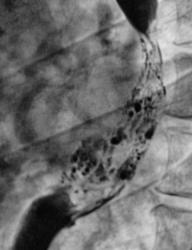

Рентгенограммы и их фрагменты.

Ниже представлены прицельные рентгенограммы пищевода, произведенные в процессе исследования данного пациента, в ортоположении водной взвесью сернокислого бария обычной консистенции.

Ниже рентгенограммы, произведенные на трохоскопе с применением сметанообразной и пастообразной контрастной взвеси.